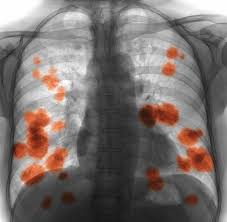

Covid 19 Coronavirus Diagnosis Chest X Ray And Ct Scan from www.verywellhealth.com Throat cancer refers cancer that develops in your throat (pharynx) or voice box (larynx). These are the headlines from several drug leaflets. The cause of the tightness can vary from an infection like strep throat to a more serious allergic. We also look at the various types and the differences between them. When you first hear about a new drug, what would you like to know about it? Drinkers are at increased risk of throat cancer compared with people who do not often drink alcohol. Though most throat cancers involve the same types of cells, specific terms are used to differentiate the part of the throat where cancer originated. Most throat cancers develop in adults older than 50.

Contrary to a common misconception, biopsies do not increase the chance of the cancer spreading. Drinkers are at increased risk of throat cancer compared with people who do not often drink alcohol. Its called throat cancer or lung cancer. Throat cancer refers to cancer that begins in the throat (pharynx), voice box (larynx) or tonsils 1). Medically reviewed by adithya cattamanchi, m.d. It's not a fracture.you see there is no swelling on my leg. Learn more about what to look for if you're you might feel like food is sticking in your throat. Lump or sore that doesn't go away. How many meals a day do you have? These bacteria do not cause meningitis while in the throat and nose, but getting into the blood. After treatment, therapy is needed to. Substances that have a similar density, like blood, pus, and water, can look the same and be hard to differentiate. What throat cancer look like.

Lump or sore that doesn't go away. Do you believe your eating habits to be healthy? Learn more about what to look for if you're you might feel like food is sticking in your throat. They do not have a clear idea as to how throat cancer looks like. Its called throat cancer or lung cancer. What can an xray show? Beams are directed at the tumor and affect only the projection area. A lump in your neck: Does he like his job? Many people mistake throat cancer with cold or sore throat. Throat cancer causes, signs and symptoms. Men are more likely than women to develop the provider may look in your throat or nose using a flexible tube with a small camera at the end. After treatment, therapy is needed to.